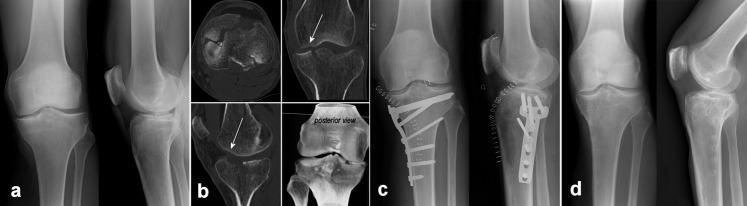

关节镜辅助下胫骨平台骨折复位内固定术(ARIF):临床和影像学中期随访。

Arthroscopically-assisted Reduction and Internal Fixation (ARIF) of tibial plateau fractures: clinical and radiographic medium-term follow-up.

Tibial plateau fractures include a wide spectrum of lesions with potentially disabling sequelae. Arthroscopically-assisted Reduction and Internal Fixation (ARIF) is an alternative to traditional ORIF. The aim of this retrospective single centre study is to evaluate medium-term clinical and radiographic outcomes achieved in a consecutive series of patients treated with ARIF.

胫骨平台骨折包括广泛的损伤范围,可能导致致残性后遗症。关节镜辅助复位内固定(ARIF)是传统切开复位内固定(ORIF)的替代方法。本回顾性单中心研究的目的是评估连续系列接受 ARIF 治疗的患者的中期临床和放射学结果。